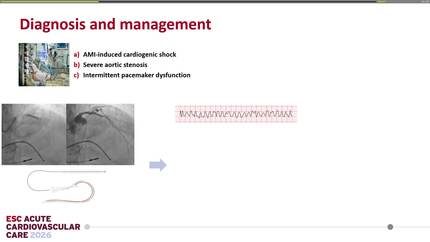

Rescue TTVR with a new-sized EVOQUE valve following transcatheter edge-to-edge repair